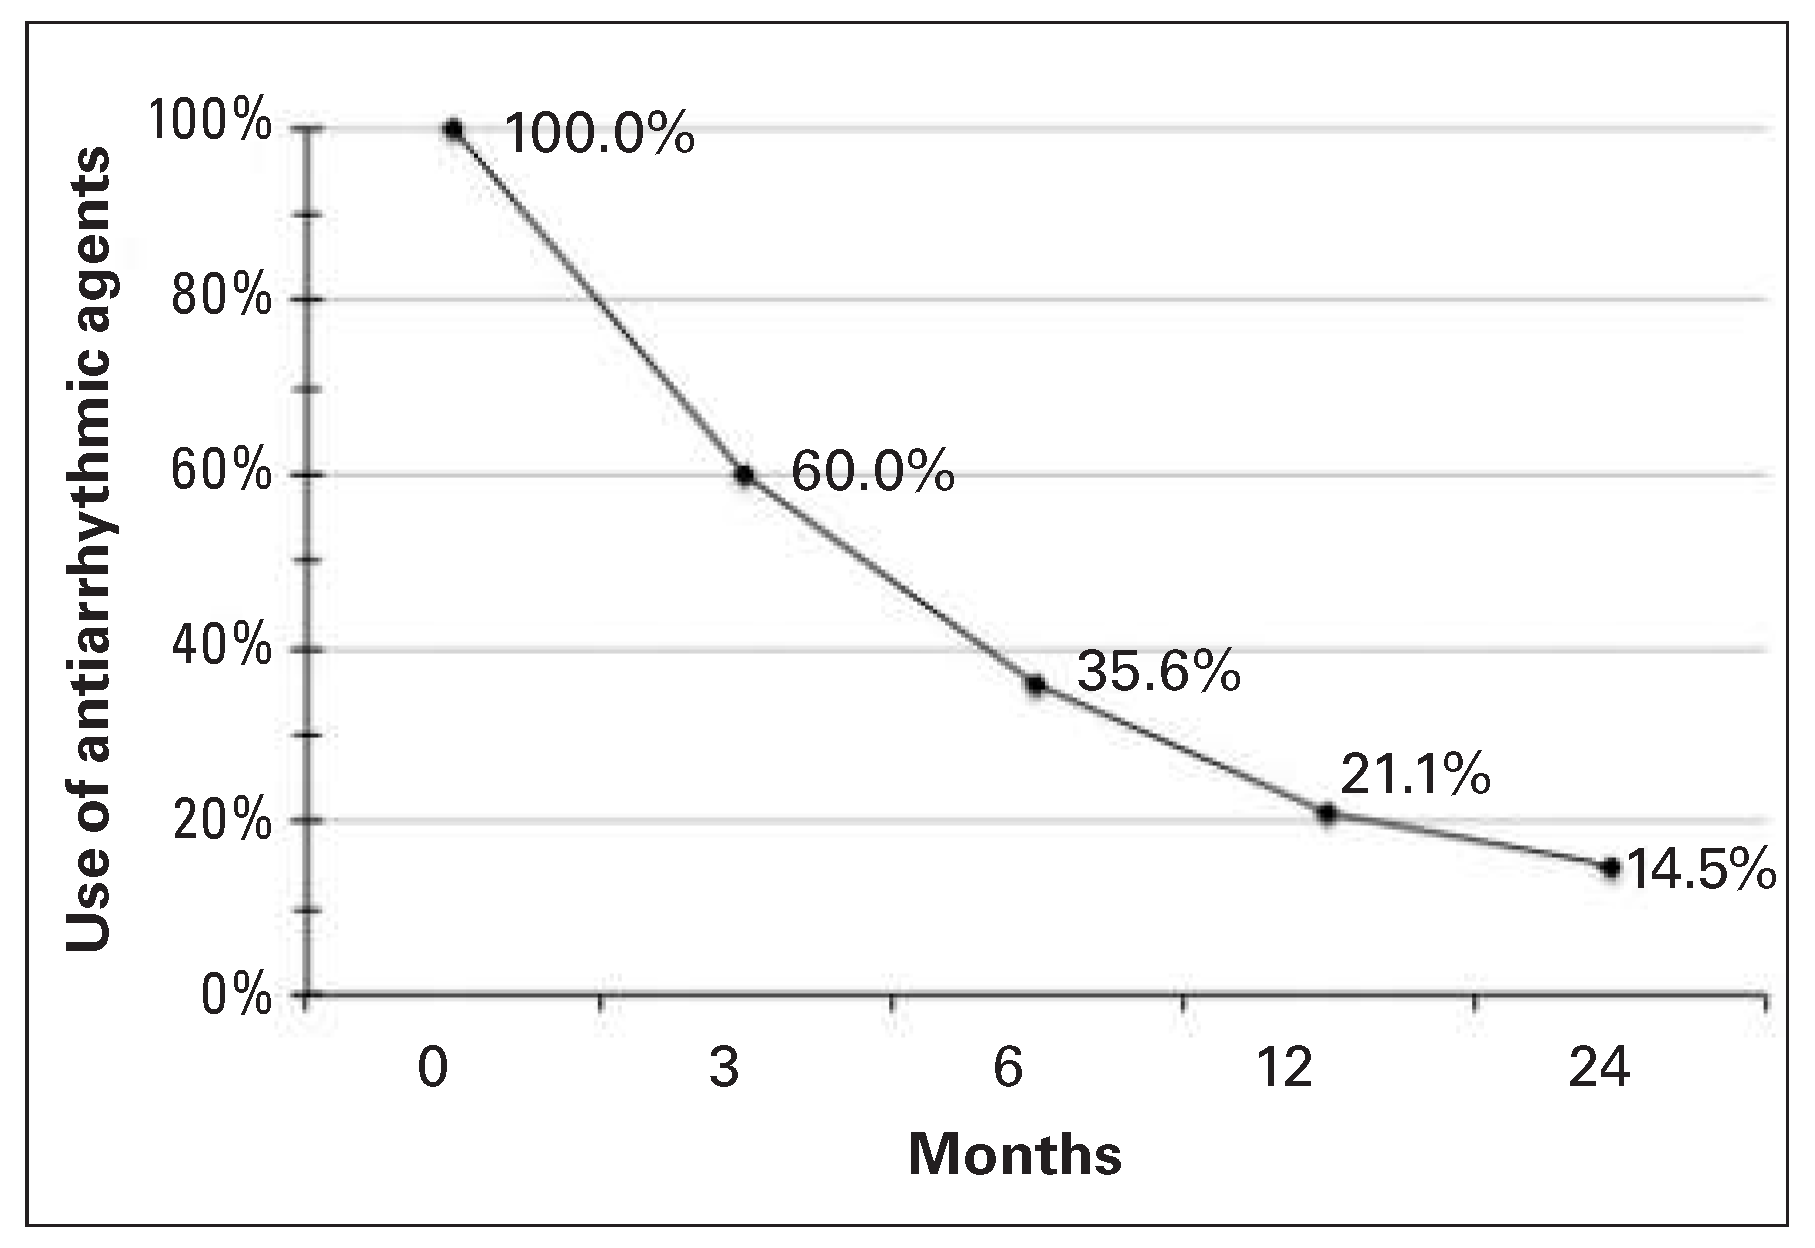

| Antiarrhythmic drugs before ablation | ||

| No antiarrhythmic drugs | 107 | 39% |

| With antiarrhythmic drugs | 168 | 61% |